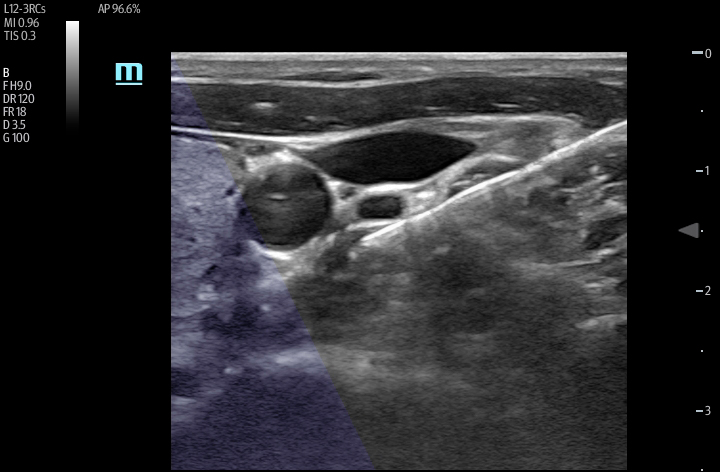

The TE7 Ultrasound System Crystal Series 2.0 is the system of choice from routine point-of-care exams to extreme situations when every second counts. With best-in-class image quality, a sleek form factor, and breakthrough needle visualization advancements, the TE7 System is designed to provide superior performance for rapid, confident exams and procedures in the fast paced, point of care environment.

The TE7 System incorporates an intuitive touchscreen and focused point-of-care protocols designed to standardize and reduce exam times. The System’s second generation iVocal voice recognition technology and new programmable-button transducer technology allows for a hands-free scanning experience, ideal for sterile environments.